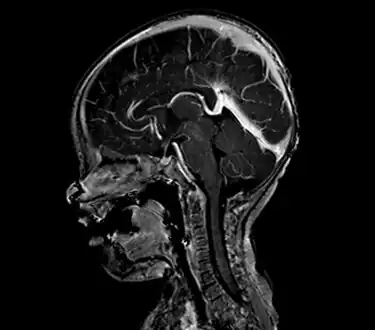

An AVM diagnosis is established by neuroimaging studies after a complete neurological and physical examination.[5][11] Three main techniques are used to visualize the brain and search for AVM: computed tomography (CT), magnetic resonance imaging (MRI), and cerebral angiography.[11] A CT scan of the head is usually performed first when the subject is symptomatic. It can suggest the approximate site of the bleed.[3] MRI is more sensitive than CT in the diagnosis of AVMs and provides better information about the exact location of the malformation.[11] More detailed pictures of the tangle of blood vessels that compose an AVM can be obtained by using radioactive agents injected into the blood stream. If a CT is used in conjunctiangiogram, this is called a computerized tomography angiogram; while, if MRI is used it is called magnetic resonance angiogram.[3][11] The best images of an AVM are obtained through cerebral angiography. This procedure involves using a catheter, threaded through an artery up to the head, to deliver a contrast agent into the AVM. As the contrast agent flows through the AVM structure, a sequence of X-ray images are obtained.[11]